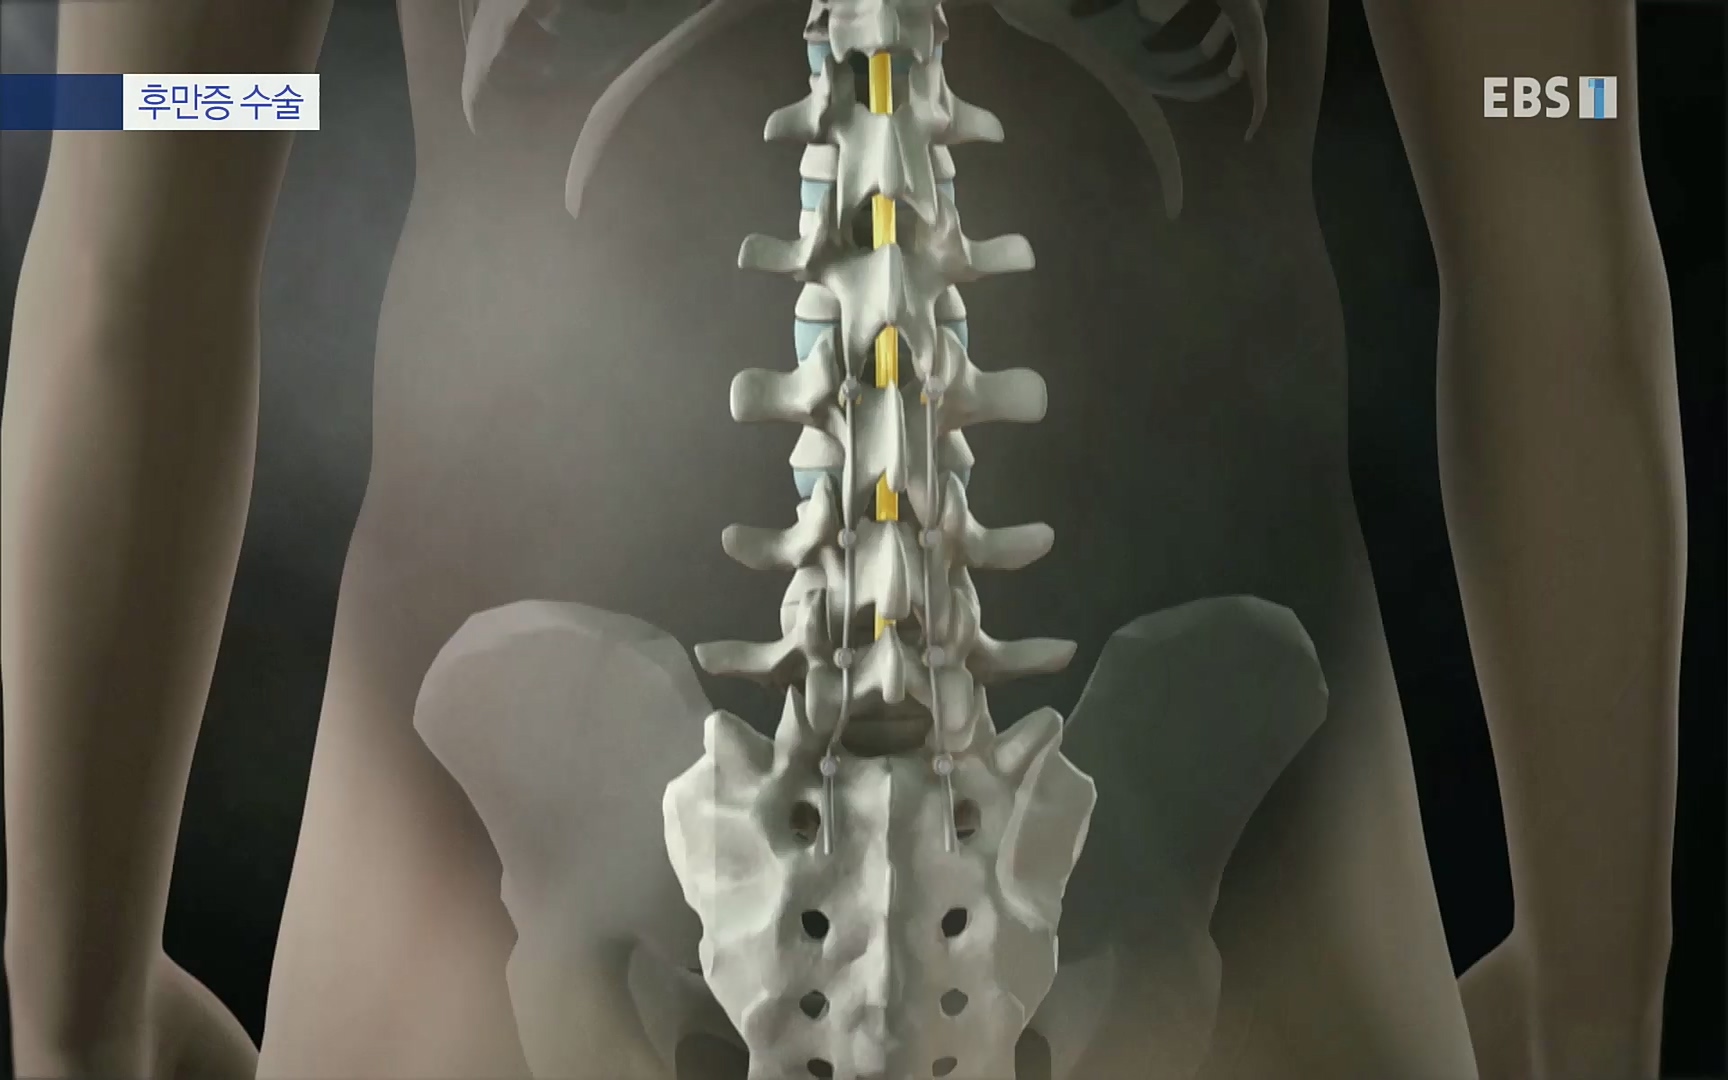

석세일 명예교수 정형외과 전문의 ·1995년 세계 최초 측만증에 척추경 나사못삽입술 시도 ㆍ척추변형에 대한 척추 후방 절제술, 척추 회전술 개발